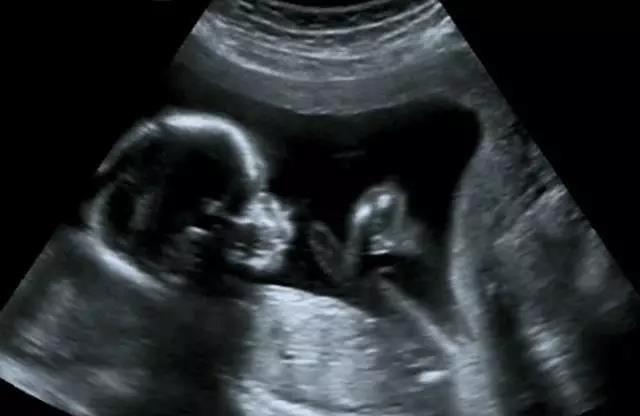

B超检查是利用超声波产生回声的原理来检查的。超声能向一定方向上传播,而且可以穿透物体,如果碰到障碍,就会产生回声,人们通过仪器将这种回声收集并显示在屏幕上,可以用来了解物体的内部结构,辅助诊断。就像挑西瓜一样,边敲边看显示病灶情况。B超是两个维度的超声信息,构成平面图形,反映人体结构。

随着彩色-多普勒超声技术的产生,出现了彩超(彩色B超),即在黑白B超的基础上加上彩色多普勒,彩超同时又提供了血流动力学的丰富信息,实际应用受到了广泛的重视和欢迎,彩超在目前临床上经常被使用。

腹腔器官受呼吸影响较大,进而影响到CT、核磁成像,而超声不会因此受影响。同时,超声对肝脏、脾脏、胰腺、肾脏、盆腔等器官诊断准确率较高。

但是超声受气体干扰很大,对于肠道等含气较多的器官,超声诊断准确率会降低。

常规的心脏结构与功能检查,心脏彩超所提供的信息已经较为充分,又简单易行。